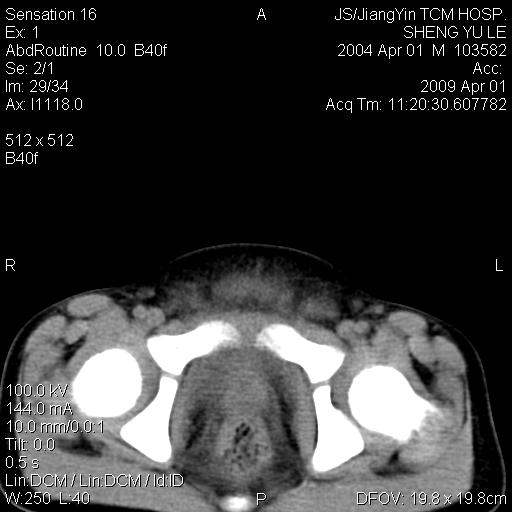

m,5岁。尿痛尿频数天。既往无病史。ct平扫腹盆腔积液。膀胱壁明显增厚。另可见心包增厚。wbc5万,骨髓穿等结果。请指教。

膀胱影像表现结合临床应该是急性膀胱炎症,但为什么有腹水呢?双肾输尿管无扩张,泌尿系压力应该不大不至于引起尿外渗,应该是腹膜感染引起的,但楼主没有提及相关症状,腹膜及膀胱结核?患者白细胞5万(结核不至于这么高啊),脾脏增大,是不是有白血病?进一步检查。。

腹水,膀胱壁增厚,wbc5万,结合临床,支持感染性疾病---感染性腹膜炎、腹水,急性膀胱炎,败血症。期待结果。